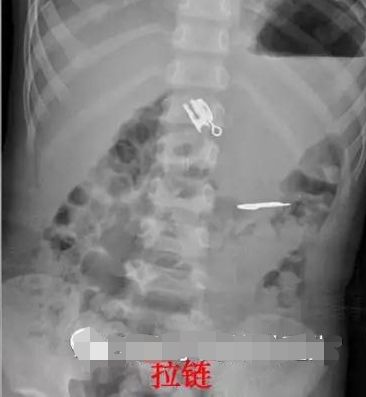

戒指、耳钉、干电池、绣花针、磁力珠、小木棒、拉链、螺丝钉……这些比较罕见的,也都是山东大学齐鲁医院(青岛)近几年接诊的消化道异物患儿中发现的。

来,眼见为实。